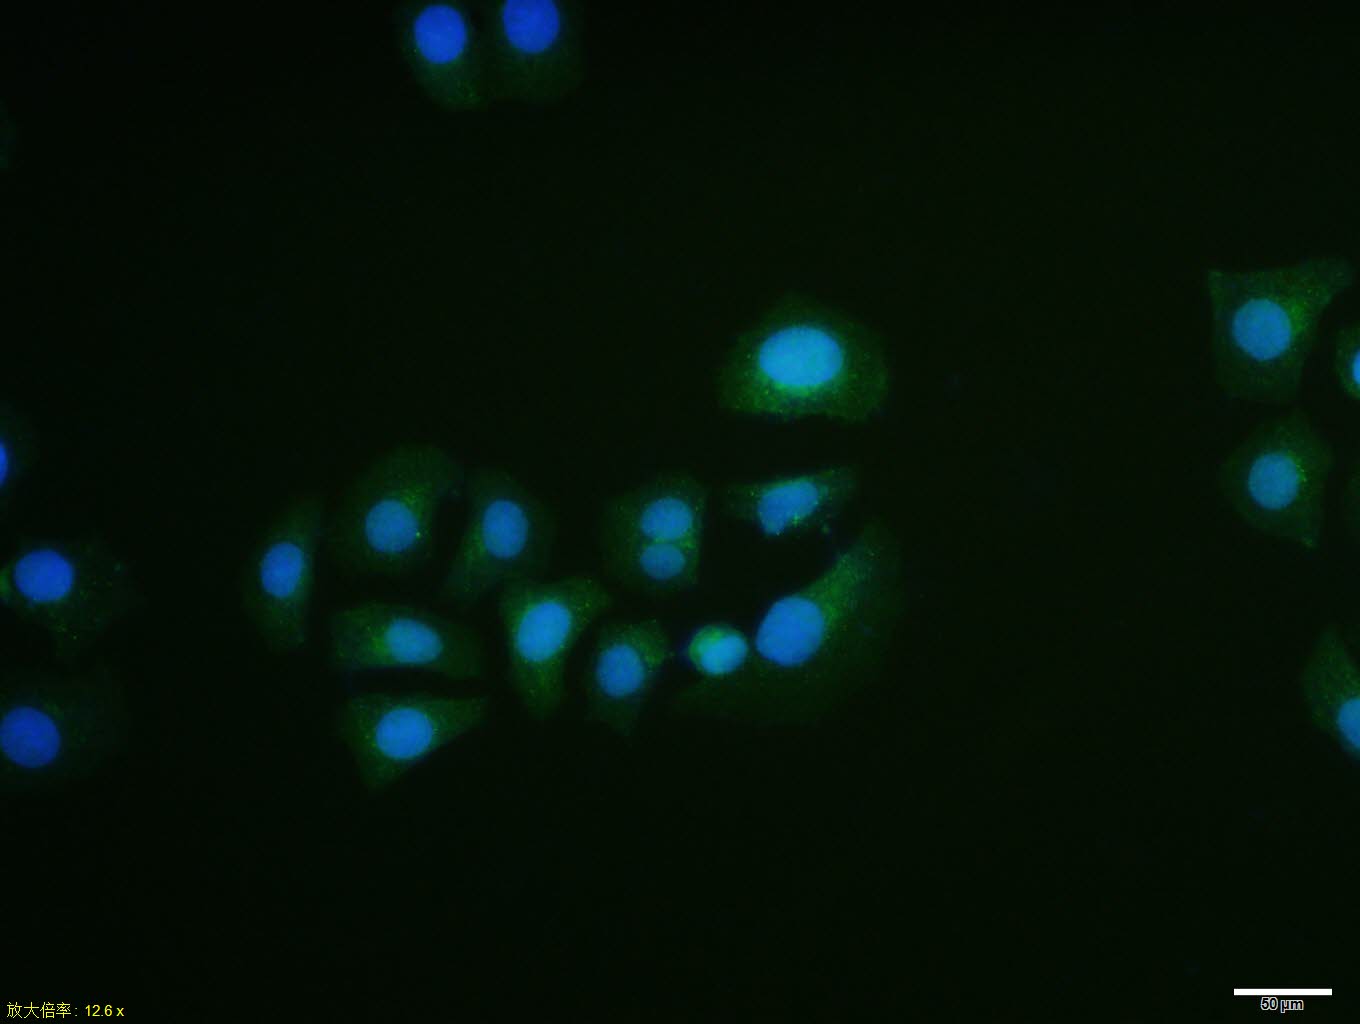

HepG2 cell; 4% Paraformaldehyde-fixed; Triton X-100 at room temperature for 20 min; Blocking buffer (normal goat serum, C-0005) at 37°C for 20 min; Antibody incubation with (Prohibitin) polyclonal Antibody, Unconjugated (bs-1449R) 1:100, 90 minutes at 37°C; followed by a conjugated Goat Anti-Rabbit IgG antibody at 37°C for 90 minutes, DAPI (blue, C02-04002) was used to stain the cell nuclei.